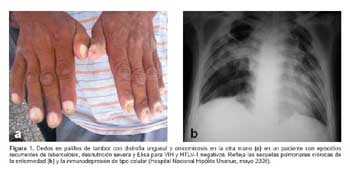

Tuberculosis: diversas manifestaciones de una misma enfermedad

Tradicionalmente se ha definido a la sífilis como la gran simuladora de las enfermedades infectocontagiosas, sin embargo la tuberculosis es igual de proteiforme en cuanto a sus manifestaciones clínicas. Esto se debe, entre otras causas, a tres factores importantes.

El primero, su capacidad de diseminación por vía hematógena y linfática. Esto le confiere la facultad de alterar la morfología y funcionamiento de virtualmente todos los órganos del cuerpo humano, incluso muchos años luego de la primo-infección, debido a su habilidad para permanecer latente en los mismos.

En segundo lugar, al tratarse de una infección intracelular, genera una respuesta inmune en la que prima ocasionalmente la liberación de citoquinas pro-inflamatorias, desencadenando procesos que pueden simular fenómenos autoinmunes. Y por último, su asociación con comorbilidades significativas que pueden ser tanto condicionantes de tuberculosis como condicionadas por la misma y que tienen su propia riqueza semiológica.

Estas manifestaciones atípicas de tuberculosis, tan variables, deben generar sospecha en el personal de salud, siendo una enfermedad muy prevalente en nuestro medio. Debemos recordar que ante un cuadro clínico raro, es más probable la manifestación atípica de una enfermedad frecuente que la manifestación típica de una enfermedad infrecuente.

Todo médico peruano debe conocer a fondo, no sólo la clásica radiografía de tórax con infiltrado apical o caverna, tan representativas de esta condición, sino también debe estar atento a solicitar las pruebas pertinentes ante posibles cuadros raros de esta enfermedad, que sin ninguna duda en los próximos años seguiremos viendo frecuentemente en los consultorios y salas de nuestros hospitales.